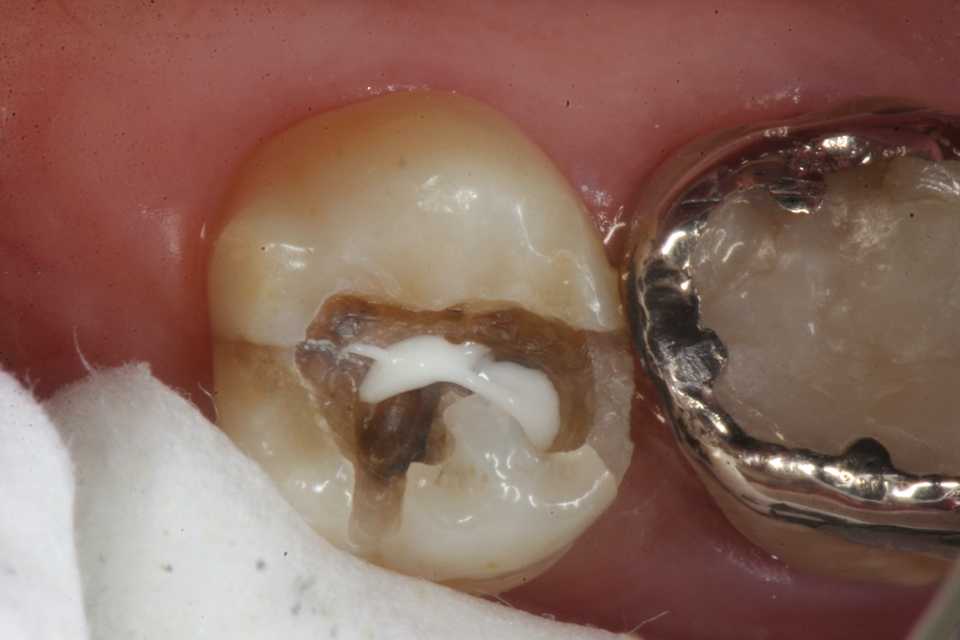

歯茎部カリエス(応力腐食割れ)0.2 2025.08.01

歯茎部カリエス(応力腐食割れ)0.1 2025.07.31

歯茎部カリエス(応力腐食割れ)0.0 2025.07.26